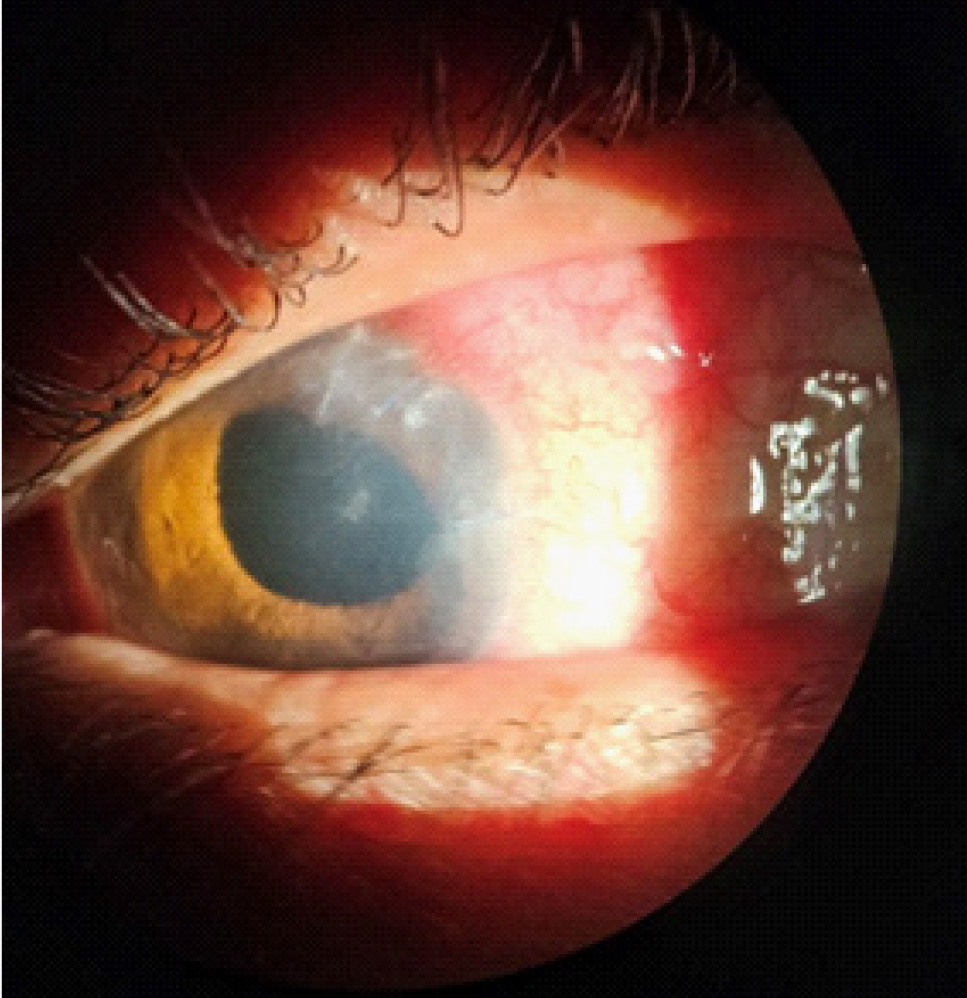

Максимально корригированная острота зрения (МКОЗ) правого глаза составляла 1.0, левого – соответствовала правильной светопроекции, пневмотонометрия OD – 19 мм рт. ст., офтальмотонус OS пальпаторно соответствовал норме. Данные биомикроскопии OD соответствовали норме. Биомикроскопия OS: отмечалась смешанная инъекция, определялись отечность роговицы и запотелость эндотелия, по меридиану 5 часов рубец, непрокрашивающийся флюоресцеином, влага передней камеры с гипопионом, в ткани радужки по меридиану 4–5 часов определялось объемное образование, реакция зрачка на свет отсутствовала (рис. 1). Визуализировалась афакия, в стекловидном теле – воспалительные клетки, детали глазного дна были трудноразличимы.

Рис. 1. Фото левого глаза на момент осмотра в приемном отделении

При послеоперационном осмотре левого глаза отмечался умеренный десцеметит, роговичные швы чистые, состоятельные, влага передней камеры прозрачная, афакия, авитрия, сетчатка прилежит (рис. 8). Острота зрения OS – правильная светопроекция, с коррекцией sph.+10,0 D составляла счет пальцев у лица на расстоянии 10 см. Пациенту рекомендовано снятие швов с роговицы в плановом порядке, а также повторный осмотр хирурга для решения вопроса о пластике радужки и вторичной имплантации ИОЛ с шовной фиксацией.

Рис. 8. Послеоперационный осмотр левого глаза